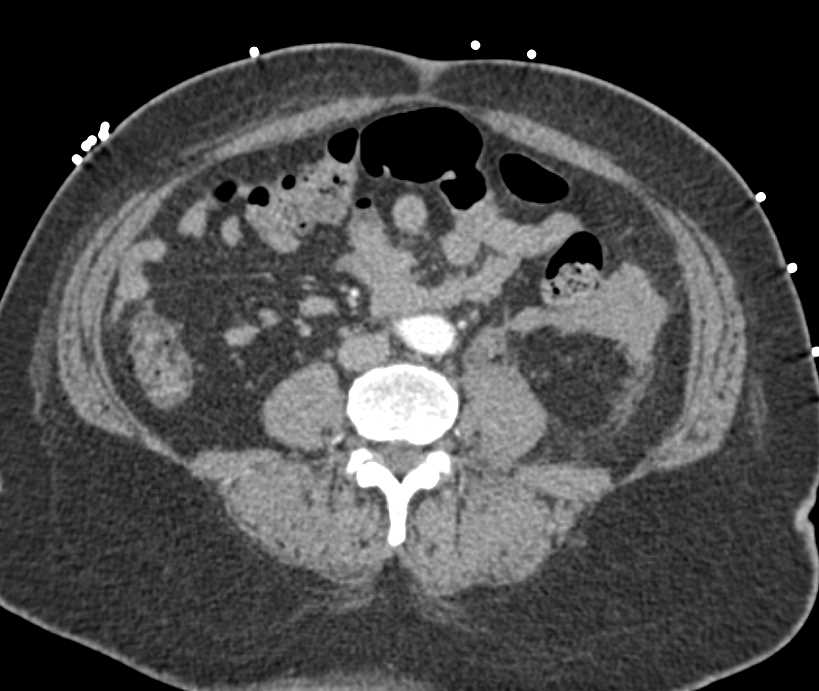

Acute Pyelonephritis Right Kidney